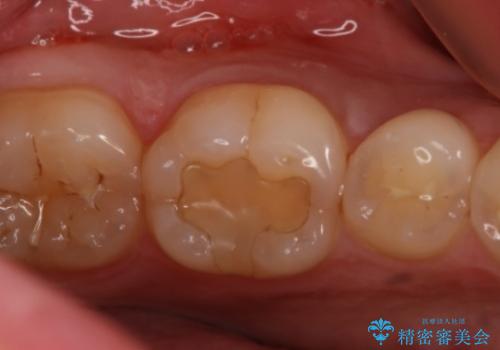

- 左下6番の治療のやり直しを希望し来院された患者様です。

保険の材料が劣化し段差や隙間ができてしまっている状態です。

自費の治療を希望されたため切削量・形態を考慮し、セラミックインレーでの治療を計画しました。